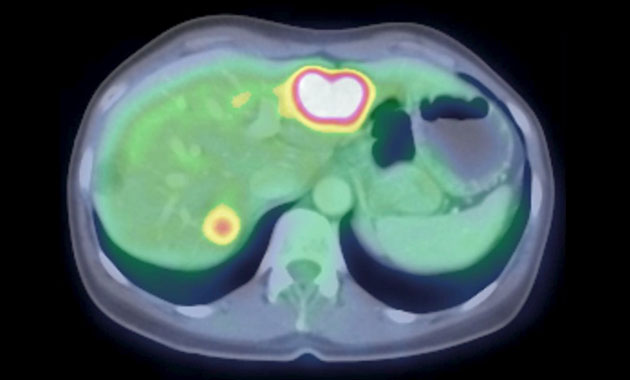

The Molecular Imaging and Therapeutics (MI&T) division, at UCSF Department of Radiology & Biomedical Imaging, oversees the clinical practice of traditional nuclear medicine, including multimodality PET/CT and PET/MR, and stewards the application of molecular therapeutic agents for our patients. The division will also work closely with the Chemistry, Probes and Molecular Therapy (CPMT) Specialized Resources Group within the department, as well as with clinicians and researchers in other departments such as oncology, cardiology and neuroscience, to usher in a new generation of imaging and treatment modalities.

- Advanced diagnostic molecular imaging modalities including new PET/CT and PET/MRI methods

- The use of cutting edge theranostic agents, which allow both imaging and therapy

- PET/CT